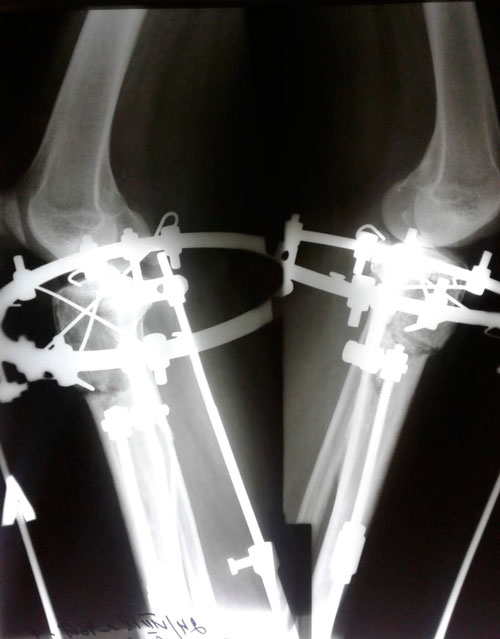

Исходник - 46 лет.

Дата операции 22.06.2018г.